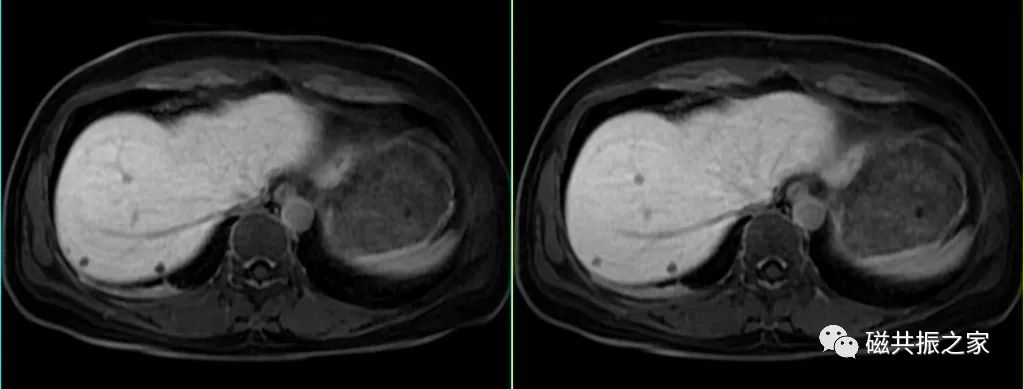

5.如采用的是肝胆特异性对比剂,肝胆期延迟扫描的时间应根据使用的对比剂类型和个体差异合理调整。

正常肝组织的信号高于血管信号,且胆系明显显影,即是较为合理的肝胆期图像。

肝硬化、肝功异常、胆道病变等,建议120min后扫描,缺乏血供小结节可延迟至3h。

同时,研究表明对于肝硬化患者,其3h后的肝胆期显示效能高于60min后的图像。

对于肝硬化、代谢异常的患者应适当延迟,建议40min后扫描。

6.在肝胆特异期使用不同的翻转角可以改善不同组织间的显示对比差异,以提高对小病灶的检出及胆道病变的显示。